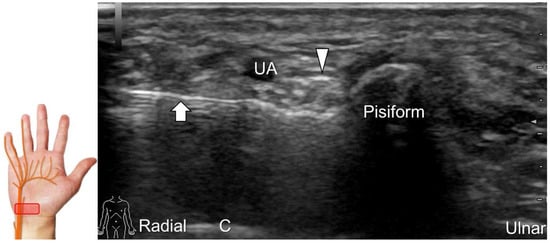

Handlebar neuropathy is a similar scenario that occurs due to continuous compression of the ulnar nerve at the ulnar wrist in cyclists. Focal swelling of the deep branch can be seen at the hamate level. An associated finding would be atrophy/weakness of the dorsal interossei muscles (Figure 16). For treatment, injection over the short axis of the ulnar nerve can be performed using the in-plane approach from the radial aspect in the Guyon’s canal (Figure 17). For certainty, identifying the ulnar artery is essential to prevent iatrogenic injury.

Figure 17. Ultrasound-guided injection of the ulnar nerve in short-axis view. Arrowhead: ulnar nerve; arrow: needle. UA: ulnar artery; C: capitate.